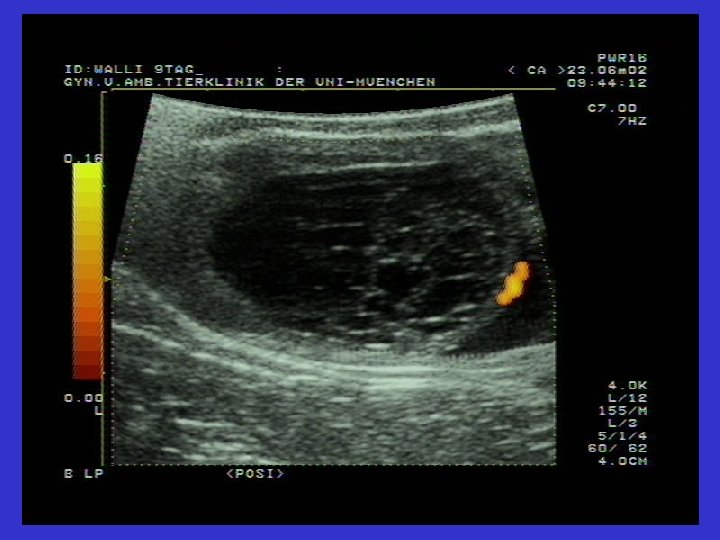

Graaf follikülü ve Follikül Theka kistlerinin karşılaştırmalı ultrasonografik görüntüsü

Ovaryum luteal kistlerinin ultrasonografik görüntüsü Solda ovaryum luteal kisti (31 mm). Gri Hipoekojenik alan çepeçevre seçiliyor.